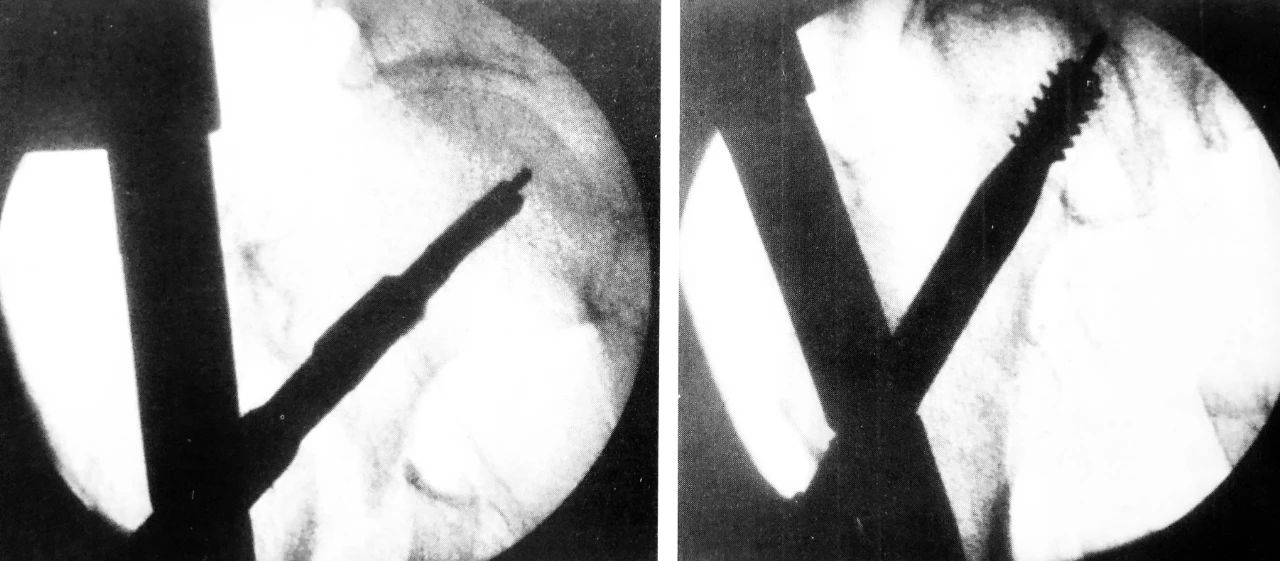

正位拉力钉导针位置、侧位拉力钉导针位置

阶梯钻钻孔、正位拉力钉位置

侧位拉力钉位置、远端锁钉置入